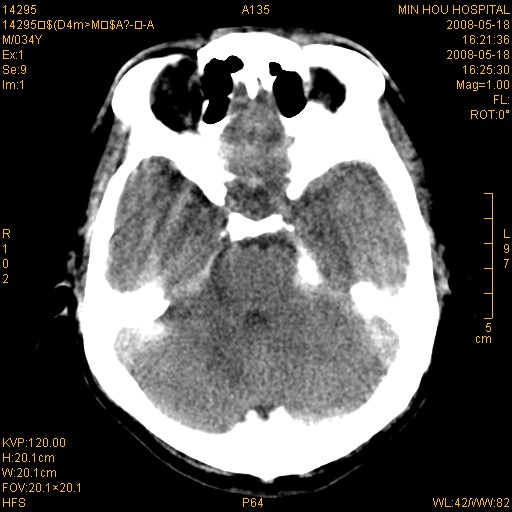

标题: CT13617:双顶叶白质水肿伴大脑镰小脑幕广泛钙化 [打印本页]

标题: CT13617:双顶叶白质水肿伴大脑镰小脑幕广泛钙化

双侧侧脑室后脚旁对称性低密度影,符合肾上腺白质营养不良(成人型)改变    小脑幕及大脑廉钙化  可考虑为生理性

支持:1、肾上腺白质营养不良.2、小脑幕、大脑镰广泛钙化。3、建议进一步检查。

硬脑膜钙化是主因,双侧顶叶白质密度减低是可能由于静脉路回流受阻所致。